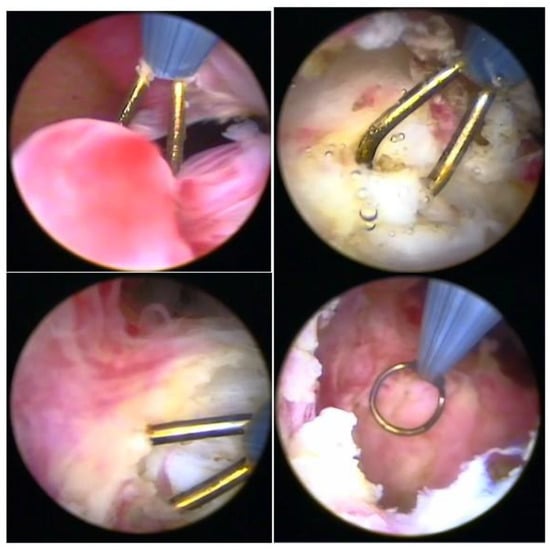

Hysteroscopy, as a method of direct visualization of the uterine cavity, offers all possible information about the intracavitary portion of the submucous myoma and a good assessment of the portion of the myoma, which is found in the myometrium, intramural portion. Thus, with hysteroscopy, it is possible to classify the submucous myoma and assess the need for other imaging methods. Another important function of hysteroscopy is to rule out other intrauterine causes of bleeding and to carry out an anatomopathological study of the endometrium or of the identified lesions, so it should, whenever possible, be indicated in the investigation (Figure 1).

Figure 1. Submucous myoma—hysteroscopic view.